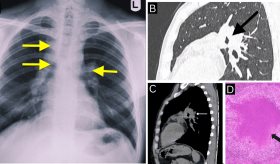

Dado que los síntomas de esta afección son similares al de las enfermedades cardíacas, pulmonares, problemas gastrointestinales y la osteoartritis, dependiendo el riesgo de cada caso, se pueden realizar exámenes para descartarlas, como un electrocardiograma o radiografía de tórax.